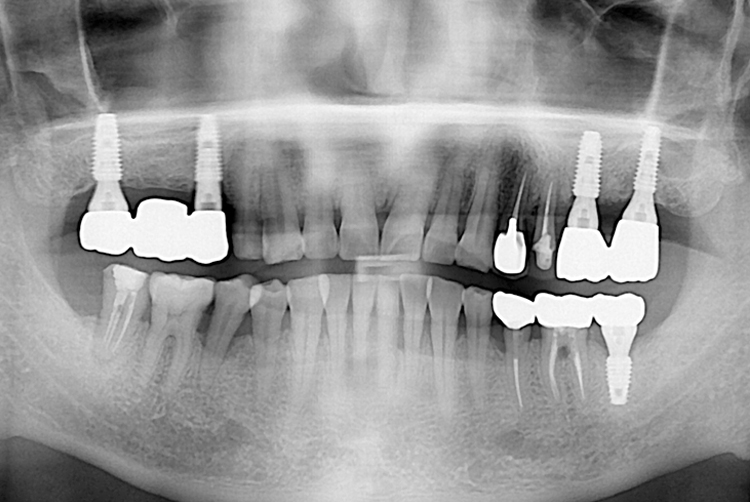

치료후 : 2019-09-19

세종치과는 많은 환자와 다양한 케이스를 바탕으로 항상 편안한 임플란트 수술을 제공하고자 노력하고,

오래동안 튼튼히 쓸 수 있는 임플란트 수술을 가장 큰 목표로 삼고 있습니다